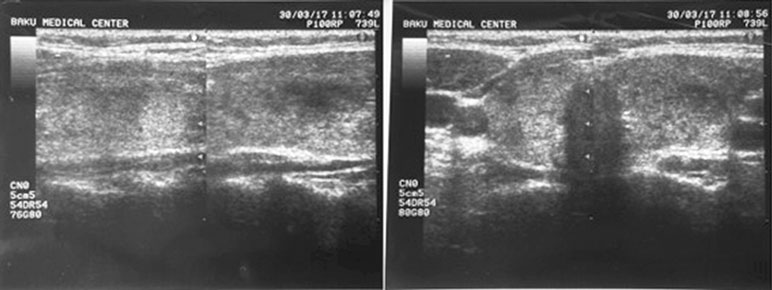

Отсутствие у пациентов основной группы признаков гипотиреоза подтверждается также клиническими наблюдениями за пациентами и данными ультразвукового исследования о состоянии ЩЖ (отсутствуют признаки увеличения органа, изменения его структуры и патологические изменения в виде формирования гипо- или гиперэхогенных участков, повышенного кровотока, уменьшается плотность и эхогенность тканей ЩЖ). А в контрольной группе сохраняются очаги гипо- и гиперэхогенности в сегментах ЩЖ и мелкоточечные гиперэхогенные включения в результате уплотнения соединительной ткани, как показано на рис. 1.

Рис. 1. Ультразвуковая картина щитовидной железы. Правая и левая доли (поперечная и продольная проекции)

По данным ультразвукового исследования ткань ЩЖ становится более однородной и изоэхогенной. Истончаются или исчезают гиперэхогенные тяжи (элементы межсегментарных перегородок и стенок сосудов). Объём железы приближается к индивидуально оптимальному.